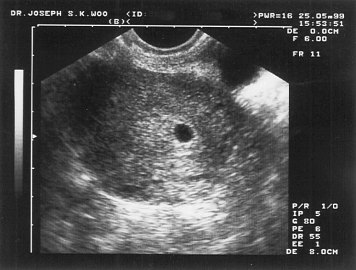

Gambar Usg Kista

MACAM-MACAM KISTA. Dari USG bisa… - dr Yudhistya SpOG | Facebook Ingin Terhindar dari Kista? Jauhi 4 Jenis Makanan Enak Ini Sekarang! - Semua Halaman - Grid Health MACAM-MACAM KISTA. Dari USG bisa… - dr Yudhistya SpOG | Facebook BILIK SONOGRAFER : Kista Ovarium MACAM-MACAM KISTA. Dari USG bisa… - dr Yudhistya SpOG | Facebook MACAM-MACAM KISTA. Dari USG bisa… - dr Yudhistya SpOG | Facebook Ahli Kista: Pastikan Kista Anda dengan USG Bagaimana mendeteksi penyakit kista ovarium? - Quora Kista Berujung Kematian, Segera Operasi ! | Daniel Kista Ovarium. - ppt download Kista 5 Kg Ibu Hamil Hilang Tanpa Operasi Halaman all - Kompasiana.com Kesha Ratuliu Ungkap Hasil USG Payudara, Jangan Tertukar, Ini Beda Tumor dan Kista - TribunStyle.com Benarkah Kista Bisa Disembuhkan dengan Kehamilan? Jangan Salah Kaprah, Ini Penjelasan Medisnya KASUS PILIHAN: KISTA COKLAT. APA ITU?… - dr Yudhistya SpOG | Facebook Dikira Cuma Masuk Angin, Dokter Ini Tercengang Saat Temukan Kista Sebesar Bola Sepak di Dalam Perut Pasiennya! - Semua Halaman - Grid.ID Punya Kista Endometriosis dan Rahim Retro, Eh HAMIL – Dessy Donat Ada kista bisa hamil juga kok… | Dr Suryo, SpOG - Kesehatan Reproduksi Kesha Ratuliu Ungkap Hasil USG Payudara, Jangan Tertukar, Ini Beda Tumor dan Kista - TribunStyle.com Kista di Rahim | Sehat PLUS Cantik Menjawab Masalah Kista Indung Telur: Bisa Hamil Apa Nggak?? Harus Operasi Apa Nggak?? (*&*^$%#%$# | Dr Suryo, SpOG - Kesehatan Reproduksi Mioma, Kista & Ambeien | Sehat PLUS Cantik Bom Waktu bernama Kista Ovarium!!! – ask-dr. David Mayndra Utama, SpOG Kisah Shireen Sungkar Punya Kista 11 Cm - Tabloidbintang.com Agar Kista Tidak Berkembang Menjadi Besar | Republika Online USG Transvaginal - Blog Positif Endometrosis - Catatannike.com Testimoni | Dr Suryo, SpOG - Kesehatan Reproduksi Kista di luar rahim.. help me bund.. - IbuHamil.com Cara Menghilangkan Penyakit Kista Ovarium Punya Kista Endometriosis dan Rahim Retro, Eh HAMIL – Dessy Donat Kenali Gejala Kista Ovarium Dikira Cuma Masuk Angin, Dokter Ini Tercengang Saat Temukan Kista Sebesar Bola Sepak di Dalam Perut Pasiennya! - Semua Halaman - Grid.ID La Rosiantes et Lahardos: Kista??? Oh Noooo… USG Ascites & Kista Ovarium Pemeriksaan abdomen pada kista ovarium - YouTube Steemit-Health #1: Kisah Operasi Kista Ovarium pada Bocah 10 Tahun (Indonesian Version) — Steemit Cara Membaca Foto USG: 8 Langkah (dengan Gambar) - wikiHow Foto Pertama USG Bukan Foto Janin | M I N E Kapan Kista Ovarium Dianggap Bahaya dan Harus Dioperasi? Kista ovarium KISTA INDUNG TELUR | 4healthylifetransferfactor 5 Fakta Kista Coklat yang Harus Diketahui | Popmama.com Kerap Makan Makanan Instan dan Pedas Tapi Jarang Makan Nasi, Perempuan Ini Alami Hal Menakutkan Sampai Harus Operasi - Semua Halaman - Nakita Miu Twitter: “Tadi abis di USG ternyata aku punya kista:") untung belum besar bgt tp tetep aja takut hehe… " 6 Tanda Anda Mengidap Kista Ovarium Retha Silaen ar Twitter: “@dr_Bambang_SpOG Dok, mau tny apakah rahim saya normal? Waktu usg transv ketika haid ada kista 2cm ktanya. Thx http://t.co/6BX9YyPMK7” Kenali Perbedaan Miom dan Kista - Investor.ID Ovarium, Ultrasonografi Ginekologi, Folikel Ovarium gambar png Penyakit Kista Indung Telur Rentan Menyerang Wanita | Xylem Penyebab Kista pada Wanita, Gejalanya hingga Cara Menghindarinya - Semua Halaman - Grid Health Jangan Takut dengan Kista Ovarium - Alodokter hasil-USG-kista-ibu eno | Nila Sari | Flickr Takut Tak Bisa Hamil Karena Kista, Shireen Sungkar Malah Hamil Anak Kedua - Banjarmasin Post Kista Bukan Kanker!! LAPORAN KASUS Kesha Ratuliu Ungkap Ukuran Tumor Payudaranya : Okezone Celebrity Assalamualaikum Bun , tadi saya baru usg soalnya bbrp Kista Dermoid Penatalaksanaan pasien pasca histerektomi Mama Ketahui Fakta Mengenai Kista saat Hamil - Mamapapa.id % Terjadi Lagi, Bayi Baru Lahir Ini ‘Mengandung’ Janin Kembarannya Sendiri Sejak dalam Kandungan - Semua Halaman - Grid Health 7 Gejala Kista Ovarium Kanan di Awal, Wanita Wajib Tahu! | Diadona.id Kista Fungsional, Bahaya Nggak Sih ? – esshintaku Tri Lestari Handayani, SKp.,M.Kep.,Sp.Mat - ppt download Penatalaksanaan pasien pasca histerektomi Ocha’s Pregnancy Diary: September 2017 Kenali Kista Ovarium Sebelum Terlambat | Dokter.my USG Ascites & Kista Ovarium Unggah Hasil USG Kesha Ratuliu Dibully, Dituding Hamil di Luar Nikah, Padahal Itu Tumor di Payudara - Pojoksatu.id Aku dan Kista Tiroid - Novarty Hamil kosong Tanpa Kuret, Ternyata Ini Dampaknya Moms! Kista endometriosis bikin down.. - IbuHamil.com Ratih Wiji Ningrum: Kista Endometriosis dan Visanne Dienogest Tumor Kandungan Mioma Kista | pengobatan penyakit tumor | gangguan kesuburan Program Hamil (Promil) | FuschiaGrey Pengalaman Menghadapi Kista Ovarium Tanpa Operasi - Ella Fitria Cara Membaca Foto USG: 8 Langkah (dengan Gambar) - wikiHow Kista Ovarium.ppt 5 Langkah Membaca Hasil USG yang Bisa Bunda Pelajari Diagnosis Mola Hidatidosa - Alomedika Kista ovarium Berhasil hamil dengan kista coklat | Dr Suryo, SpOG - Kesehatan Reproduksi Obat Herbal untuk Kista dan Miom Paling AMPUH dan AMAN - Posts | Facebook Penyebab Kista Ovarium dan Gejalanya - Mamapapa.id % Kista? Glucogen Solusinya - Irma Vania Oesmani MELAWAN KISTA RAHIM / KISTA OVARIUM : apa itu? dan bagaimana saya mengatasinya? | Yubikanobi DUA MINGGU SAJA KISTA HILANG, SAYA HAMIL | Breakthrough Generation Nyeri Perut karena Kista 10cm Mengecil dengan Varash Classic – Varashoil USG Transrektal Adalah Sejenis USG Panggul, Apa Fungsinya? kista | Dr Suryo, SpOG - Kesehatan Reproduksi Kenali Perbedaan Tes USG Abdominal dan Transvaginal Semua Akan Terjawab di Waktu yang Tepat - kumparan.com Ocha’s Pregnancy Diary: HASIL USG PERTAMA lapkas kista ginjal Cara Membaca Foto USG: 8 Langkah (dengan Gambar) - wikiHow Penyakit Kista Dentigerous - Gejala, Penyebab, Pengobatan - Klikdokter.com Biaya USG untuk penyakit dalam - YouTube Unggah Foto USG, Kesha Ratuliu Dikira Hamil Padahal Belum Nikah. Ternyata itu Bukan Foto Rahim April | 2015 | Dr Suryo, SpOG - Kesehatan Reproduksi | Page 2 Penatalaksanaan pasien pasca histerektomi